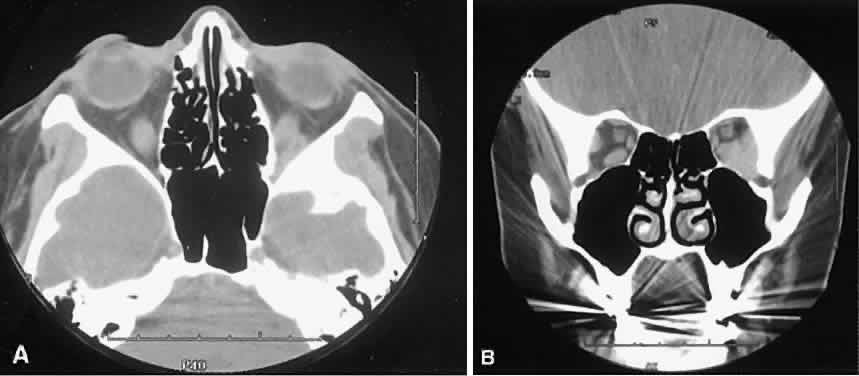

Graves' orbitopathy probably represents the most frequent cause of proptosis and EOM enlargement. The CT findings are fairly stereotyped and typically display various degrees of EOM enlargement (Fig. 7). The inferior rectus muscle usually is affected earliest, followed by the medial rectus, superior rectus, and finally the lateral rectus muscle. Rootman and colleagues13 noted more frequent involvement of the superior rectus/levator and medial rectus muscles than what had been reported previously with Graves' orbitopathy. These muscles can be affected in isolation, with the exception of the lateral rectus. To the best of our knowledge, isolated lateral rectus enlargement has not been reported in Graves' orbitopathy and in our experience usually is associated with a sphenoid wing meningioma.

Fig. 7. Graves' orbitopathy with two variations. Axial (A) and coronal (B) views show symmetric fusiform enlargement of the extraocular muscles with tapered muscle insertions. Note the predominant enlargement of the inferior, medial, and superior rectus muscles with lesser involvement of the lateral rectus muscle, a frequent pattern of enlargement in Graves' orbitopathy. Axial (C) and coronal (D) views of Graves' orbitopathy with expansion of retrobulbar ground substance and relative sparing of the extraocular muscles.